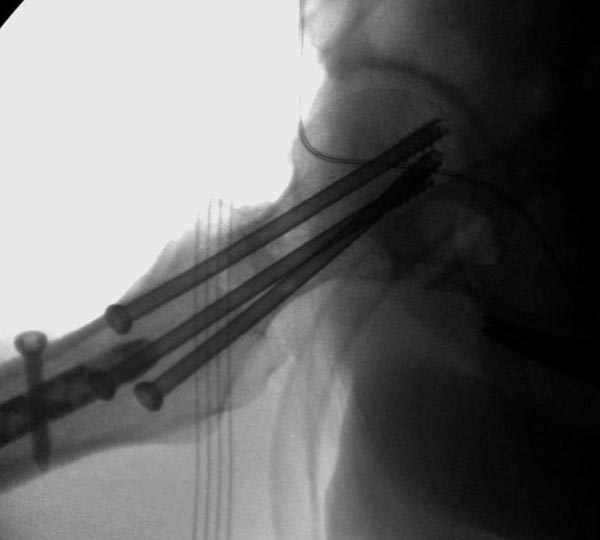

Здесь выставлен ренгенограммы больного, ему 21, травму получил в

результате высокоскоростной погони на украденной машине, которая

закончилась смертью трех остальных“боевых комрадов”. Начатую коллегой

открытую операцию на шейке пришлось закончить мне, установкой винтов и

ретроградной фиксацией бедра. Выписка в обычное сроки и наблюдался

амбулаторно. Каждый раз напоминали о возможности осложнений ввиде

несращения! По истечению 4 месяцев появились признаки варусной

деформации. На СТ срезах несращение шейки и бедра. Риминг, замена на

более толстый гвоздь и вальгусная остеотомия.